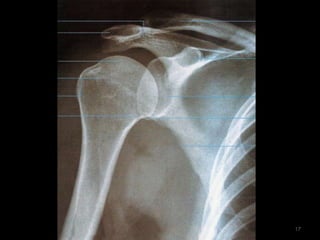

Ombro14

Incidência AP Ombro Rotação Neutra (1)15

16

17

Incidência AP- Ombro Verdadeiro(2)18